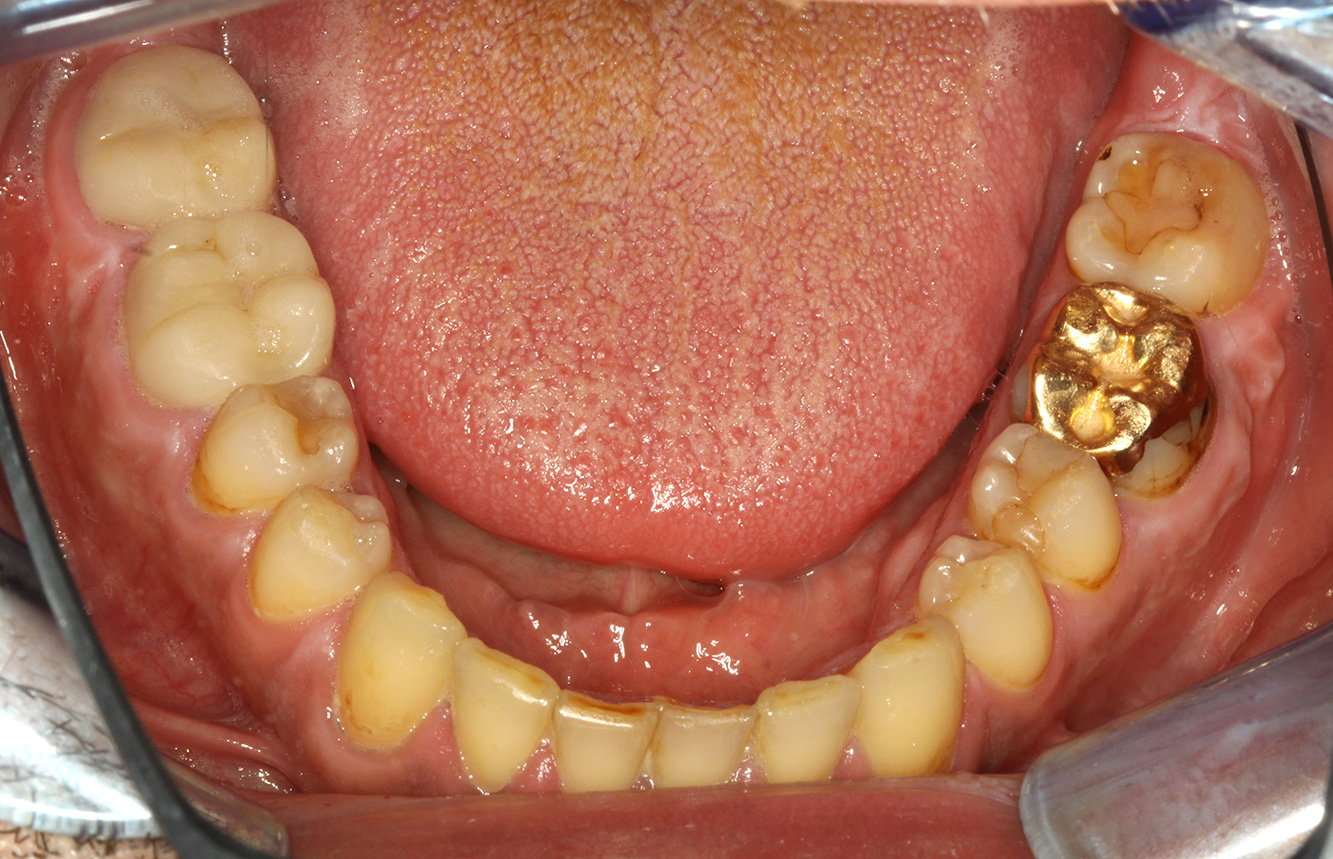

Der Transplantationspatient mit Gingivawucherungen

Ein 71-jähriger Patient mit Z.n. Nierentransplantation und Hypertonie (Bluthochdruck) stellt sich vor. Bedingt durch die Krankengeschichte ist eine Dauermedikation mit Cyclosporin, zur Unterdrückung der Immunabwehr, und Amlodipin, zur Blutdrucksenkung, erforderlich. Außerdem berichtet der Patient über empfindliches Zahnfleisch und Zahnfleischbluten. Aus mundgesundheitlicher Sicht zeigt sich ein saniertes Gebiss mit acht fehlenden Zähnen, ausgeprägte Gingivawucherungen, eine Parodontitis Stadium II, Grad B mit aktiven Taschen und eine initiale Wurzelkaries an Zahn 22. In der Kariesrisikoabschätzung wird ein mittleres Kariesrisiko (API 60) festgestellt. Für die Prophylaxesitzung lassen sich folgende Behandlungsempfehlungen ableiten. mehr Infos